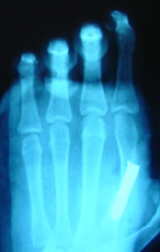

Isolated Ectrodactyly/Split Hand-Feet Malformation: About Two Cases

Abir Lemrabet, Hajar Zebbakh, Najlae Lrhorfi, Nazik Allali and Latifa Chat. 14(7): 41-44.